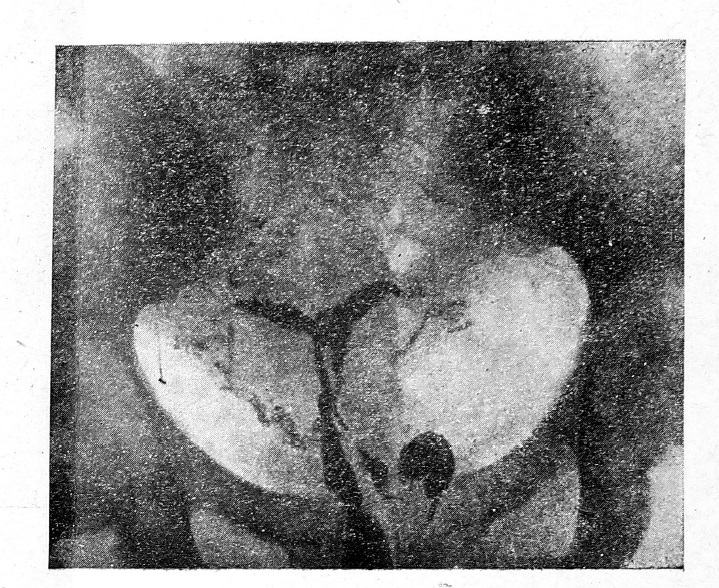

Мы уже упоминали, что в вопросе изучения анатомии матки метросальпинтография является одним из наиболее ценных методов: это относится в значительной степени и к выявлению при помощи этого метода различных вариантов и аномалий матки. На нашем материале нам удалось выявить 2 двурогих матки (рис. 5) и несколько приближающихся по своей форме к двурогим. Видимо, этот вариант встречается чаще, чем полагают.

Рис. 5